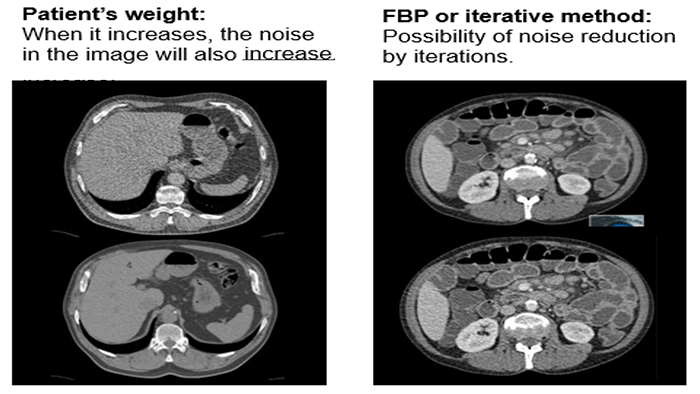

When the patient’s weight increases the noise in the image will also increase. Increasing the kVp or mA will not improve the noise.

Various metal artifact reduction techniques have been developed to reduce metal artifacts, and the most commonly used reconstruction algorithm for CT has filtered back projection (FBP), interpolation methods, and iterative reconstruction methods.

Signal to Noise Ratio and Dose

When the slices are thicker, the information is averaged. We then lose spatial resolution but gain in the signal to noise ratio.

Iterative reconstruction and denoising techniques facilitate CT radiation dose reduction because they reduce image noise, which is one of the limiting factors of dose reduction.